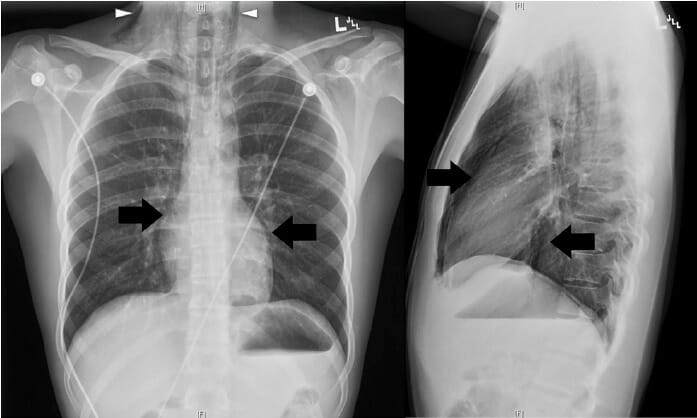

No mediastino mûˋdio:

- Adenomegalias: aumento dos vasos linfûÀticos (linfomas, doenûÏas inflamatû°rias);

- Cistos.